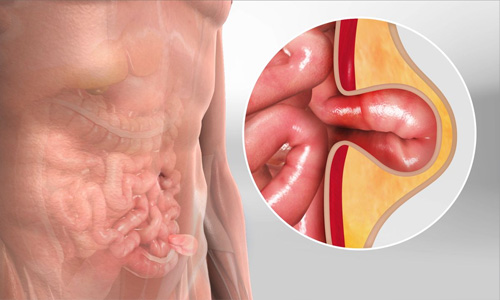

Hernia Surgery

A hernia is a bulge or swelling that happens as an inner body part pokes through a weak area of muscle or tissue wall. A hernia means something..